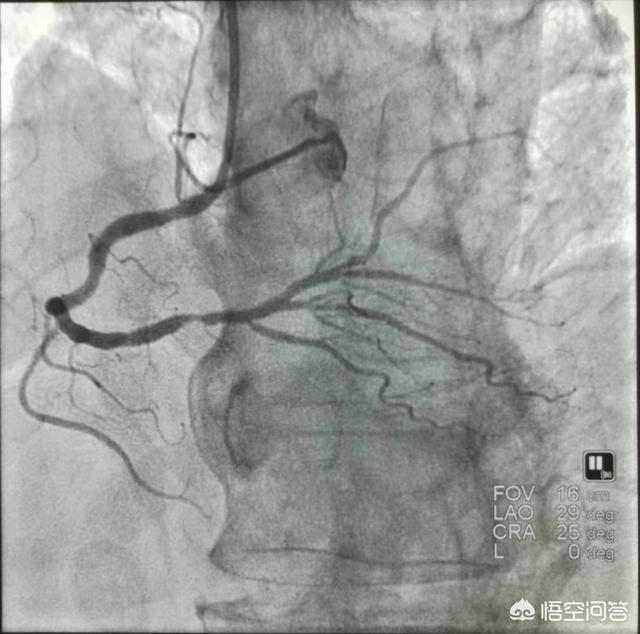

4. la coronarographie. La coronarographie reste l'examen de référence pour le diagnostic des maladies coronariennes, mais elle est invasive et nécessite une hospitalisation.

2. angiographie coronaire

Il s'agit actuellement de l'étalon-or du dépistage cardiovasculaire, qui est intuitif et permet de connaître à temps les interventions, mais il est coûteux et peut être dangereux.

Tante Li a été admise à l'hôpital pour une oppression thoracique et un essoufflement depuis plus d'un an, avec une dyspnée paroxystique nocturne et un œdème des deux membres inférieurs, et a été considérée comme souffrant d'une insuffisance cardiaque. La tomodensitométrie thoracique a révélé une hypertrophie de l'ombre cardiaque et une stase pulmonaire. L'échographie cardiaque bidimensionnelle a révélé une hypertrophie du système cardiaque gauche, une diminution de la fonction systolique du ventricule gauche et une élévation du NT~proBNP. Une coronarographie complémentaire a montré une sténose sévère de la branche descendante antérieure proximale. Une insuffisance cardiaque due à une cardiomyopathie ischémique coronaire a été envisagée.

Chez un patient atteint d'une maladie coronarienne, un électrocardiogramme bien établi, un électrocardiogramme ambulatoire et une épreuve d'effort sont nécessaires pour déterminer indirectement l'ischémie myocardique. L'échographie cardiaque 2D permet de déterminer s'il existe une ischémie myocardique en fonction du mouvement de la paroi ventriculaire. La scintigraphie nucléaire du myocarde peut déterminer s'il y a une ischémie myocardique par la présence de défauts de remplissage et peut également déterminer la fonction cardiaque. L'angio-tomodensitométrie coronaire (CT angiography) et la coronarographie permettent de déterminer l'emplacement et l'étendue des sténoses et des calcifications. L'infarctus aigu du myocarde est également pris en compte pour améliorer les marqueurs de lésions myocardiques.

Deuxièmement, l'imagerie. L'angiographie est principalement une coronarographie, qui est une technique d'examen relativement avancée permettant de détecter la portée et l'étendue des lésions des artères coronaires.

IV. angiographie coronaire

La coronarographie est la technique de référence pour le diagnostic de la maladie coronarienne. Elle permet d'observer et d'évaluer visuellement le trajet et la perméabilité des vaisseaux des artères coronaires, d'évaluer la présence ou l'absence de lésions des artères coronaires et l'étendue des lésions, et d'évaluer la fonction du cœur gauche, ce qui permet d'effectuer une thérapie interventionnelle en fonction de l'étendue des lésions des artères coronaires et d'évaluer l'effet du pontage coronarien et de la thérapie post-interventionnelle. En tant que technique diagnostique invasive, la coronarographie présente certaines contre-indications, telles que l'allergie à l'iode et au produit de contraste, l'insuffisance cardio-pulmonaire sévère, l'insuffisance hépatique et rénale, l'arythmie cardiaque et les troubles électrolytiques, qui ne peuvent pas être effectuées afin d'éviter les accidents.